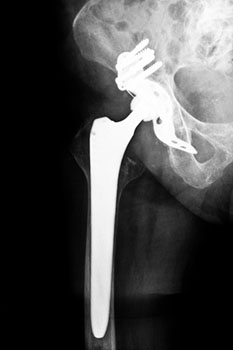

A ball-and-socket joint looks exactly like it sounds, like a ball in a concave space. These joints allow bones to move in a circular way. They are found between the femur and pelvis, as shown in this human pelvis, as well as in the shoulder. Pivot Joint